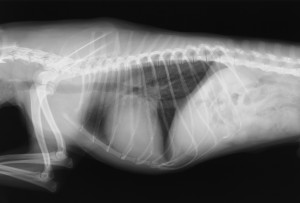

左の画像は犬の胸部 X 線画像です。

この子は健診で心雑音が聴取されたため、心臓の検査を行いました。結果、心拡大はあるものの、症状は無い状態(ACVIM 分類のステージ B2)だったので、血管 拡張薬の投薬を開始しました。